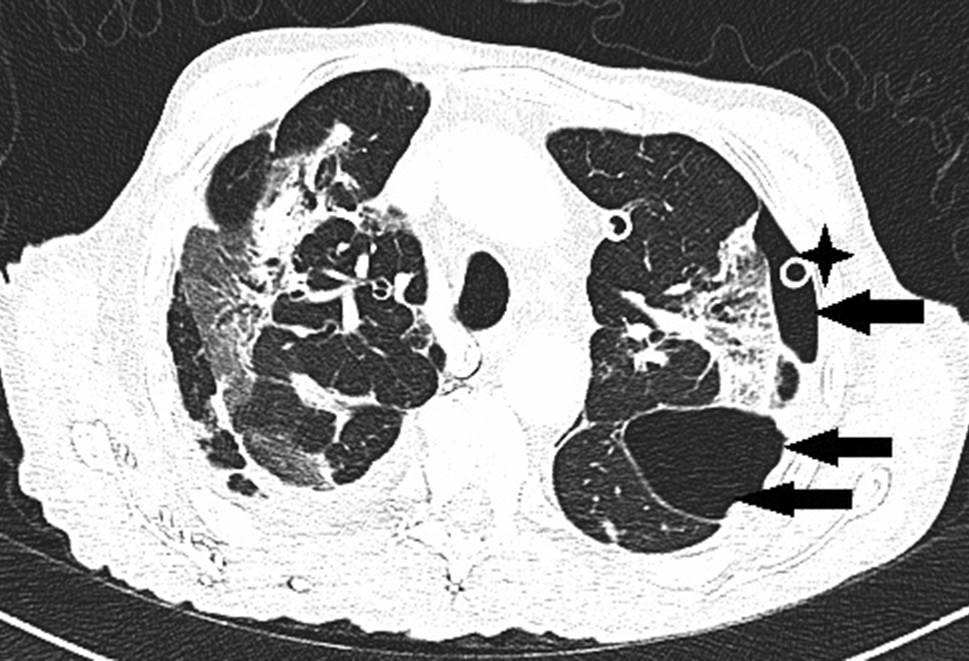

Ein 71-jähriger Patient wurde aufgrund rasch zunehmender respiratorischer Insuffizienz aufgenommen. Das Thorax-CT bei der Aufnahme zeigte bilaterale milchglasartige Verschattungen mit Punctum maximum in den Unterlappen (Abb. 1). Die PCR bestätigte die Infektion mit SARS-CoV‑2. Seit 9 Tagen bestanden Myalgien, Diarrhö und Anosmie. Anamnestisch lag Asthma bronchiale unter Bedarfstherapie vor. Die Kreislaufparameter waren unauffällig, die Temperatur subfebril. Unter Raumluft war die Sauerstoffsättigung 78 %, unter 9 l O2/min Maskenatmung 92 %. Die Atemfrequenz war auf 52/min gesteigert. Im Labor waren CRP auf 104 mg/l (Normwert 0–5), Ferritin auf 2295 ng/ml (NW 18–360) und IL 6 auf 133 pg/ml (NW 0–7) erhöht. Nach Einleitung antibiotischer, antimykotischer und antiviraler Therapie mit Ampicillin/Sulbactam, Azithromycin und Posaconazol, sowie Dexamethason, Remdesivir und Aciclovir wurde der Patient an der Intensivstation aufgenommen.

Abb. 1

SARS-CoV‑2-Pneumonie: Milchglasverschattungen (Pfeile)

Nach 24 h nichtinvasiver Beatmungsversuche war wegen rasch progredienter, respiratorischer Verschlechterung die Intubation erforderlich. Durch Bauchlagerung und Optimierung der Beatmungsparameter gelang eine vorübergehende Stabilisation der Oxygenierung mit Oxygenationsindizes (OI) bis 150. Am Tag 13 fiel ein rasch progredientes Weichteilemphysem an Hals und linkem Hemithorax auf. Das Thorax-CT zeigte multiple Milchglastrübungen („ground-glass opacity“), Parenchymkonsolidierungen sowie einen schmalen Pneumothorax links mit einer apikalen Spaltbreite bis maximal 15 mm. Zusätzlich bestanden ein ausgedehntes Pneumomediastinum und bilaterales Weichteilemphysem am Thorax (Abb. 2). Nach Anlage einer linksseitigen Thoraxdrainage war das Weichteilemphysem zunächst rückläufig. Wegen dessen erneuter, rascher Zunahme wurden rechts und links je eine weitere Thoraxdrainage gelegt, obwohl rechts kein Pneumothorax nachweisbar war. Danach war das Weichteilemphysem kontinuierlich regredient, die Lungen blieben expandiert. Trotzdem verschlechterte sich die respiratorische Situation unaufhaltsam. Der Patient verstarb nach 17 Tagen invasiver Beatmung (Pressure-Support-Ventilation-Modus, Spitzendrücke 28 mbar, durchschnittlicher „driving pressure“ 17 mbar) und begleitender, intensivmedizinischer Maßnahmen infolge kardiorespiratorischen Versagens.

Abb. 2

Ausgedehntes Pneumomediastinum (Pfeil) bei nur minimal ausgeprägtem Pneumothorax (2 Pfeile). Weichteilemphysem am gesamten Thorax (Sterne)